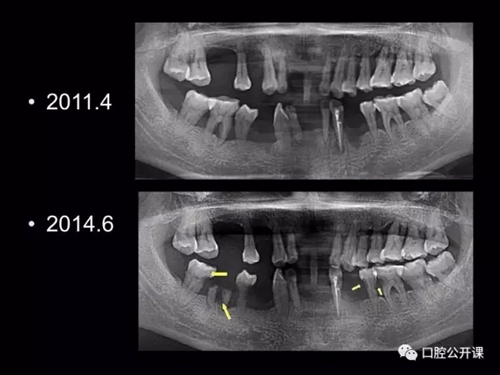

一例廣泛型侵襲性牙周炎5年臨床追蹤下

楊淑銀醫(yī)師用他的一例侵襲性牙周炎五年臨床病例追蹤來縮影一個青年牙周醫(yī)師的成長之路,帶我們一起探索看似平凡枯燥的牙周基礎治療到底有怎樣的重要性?